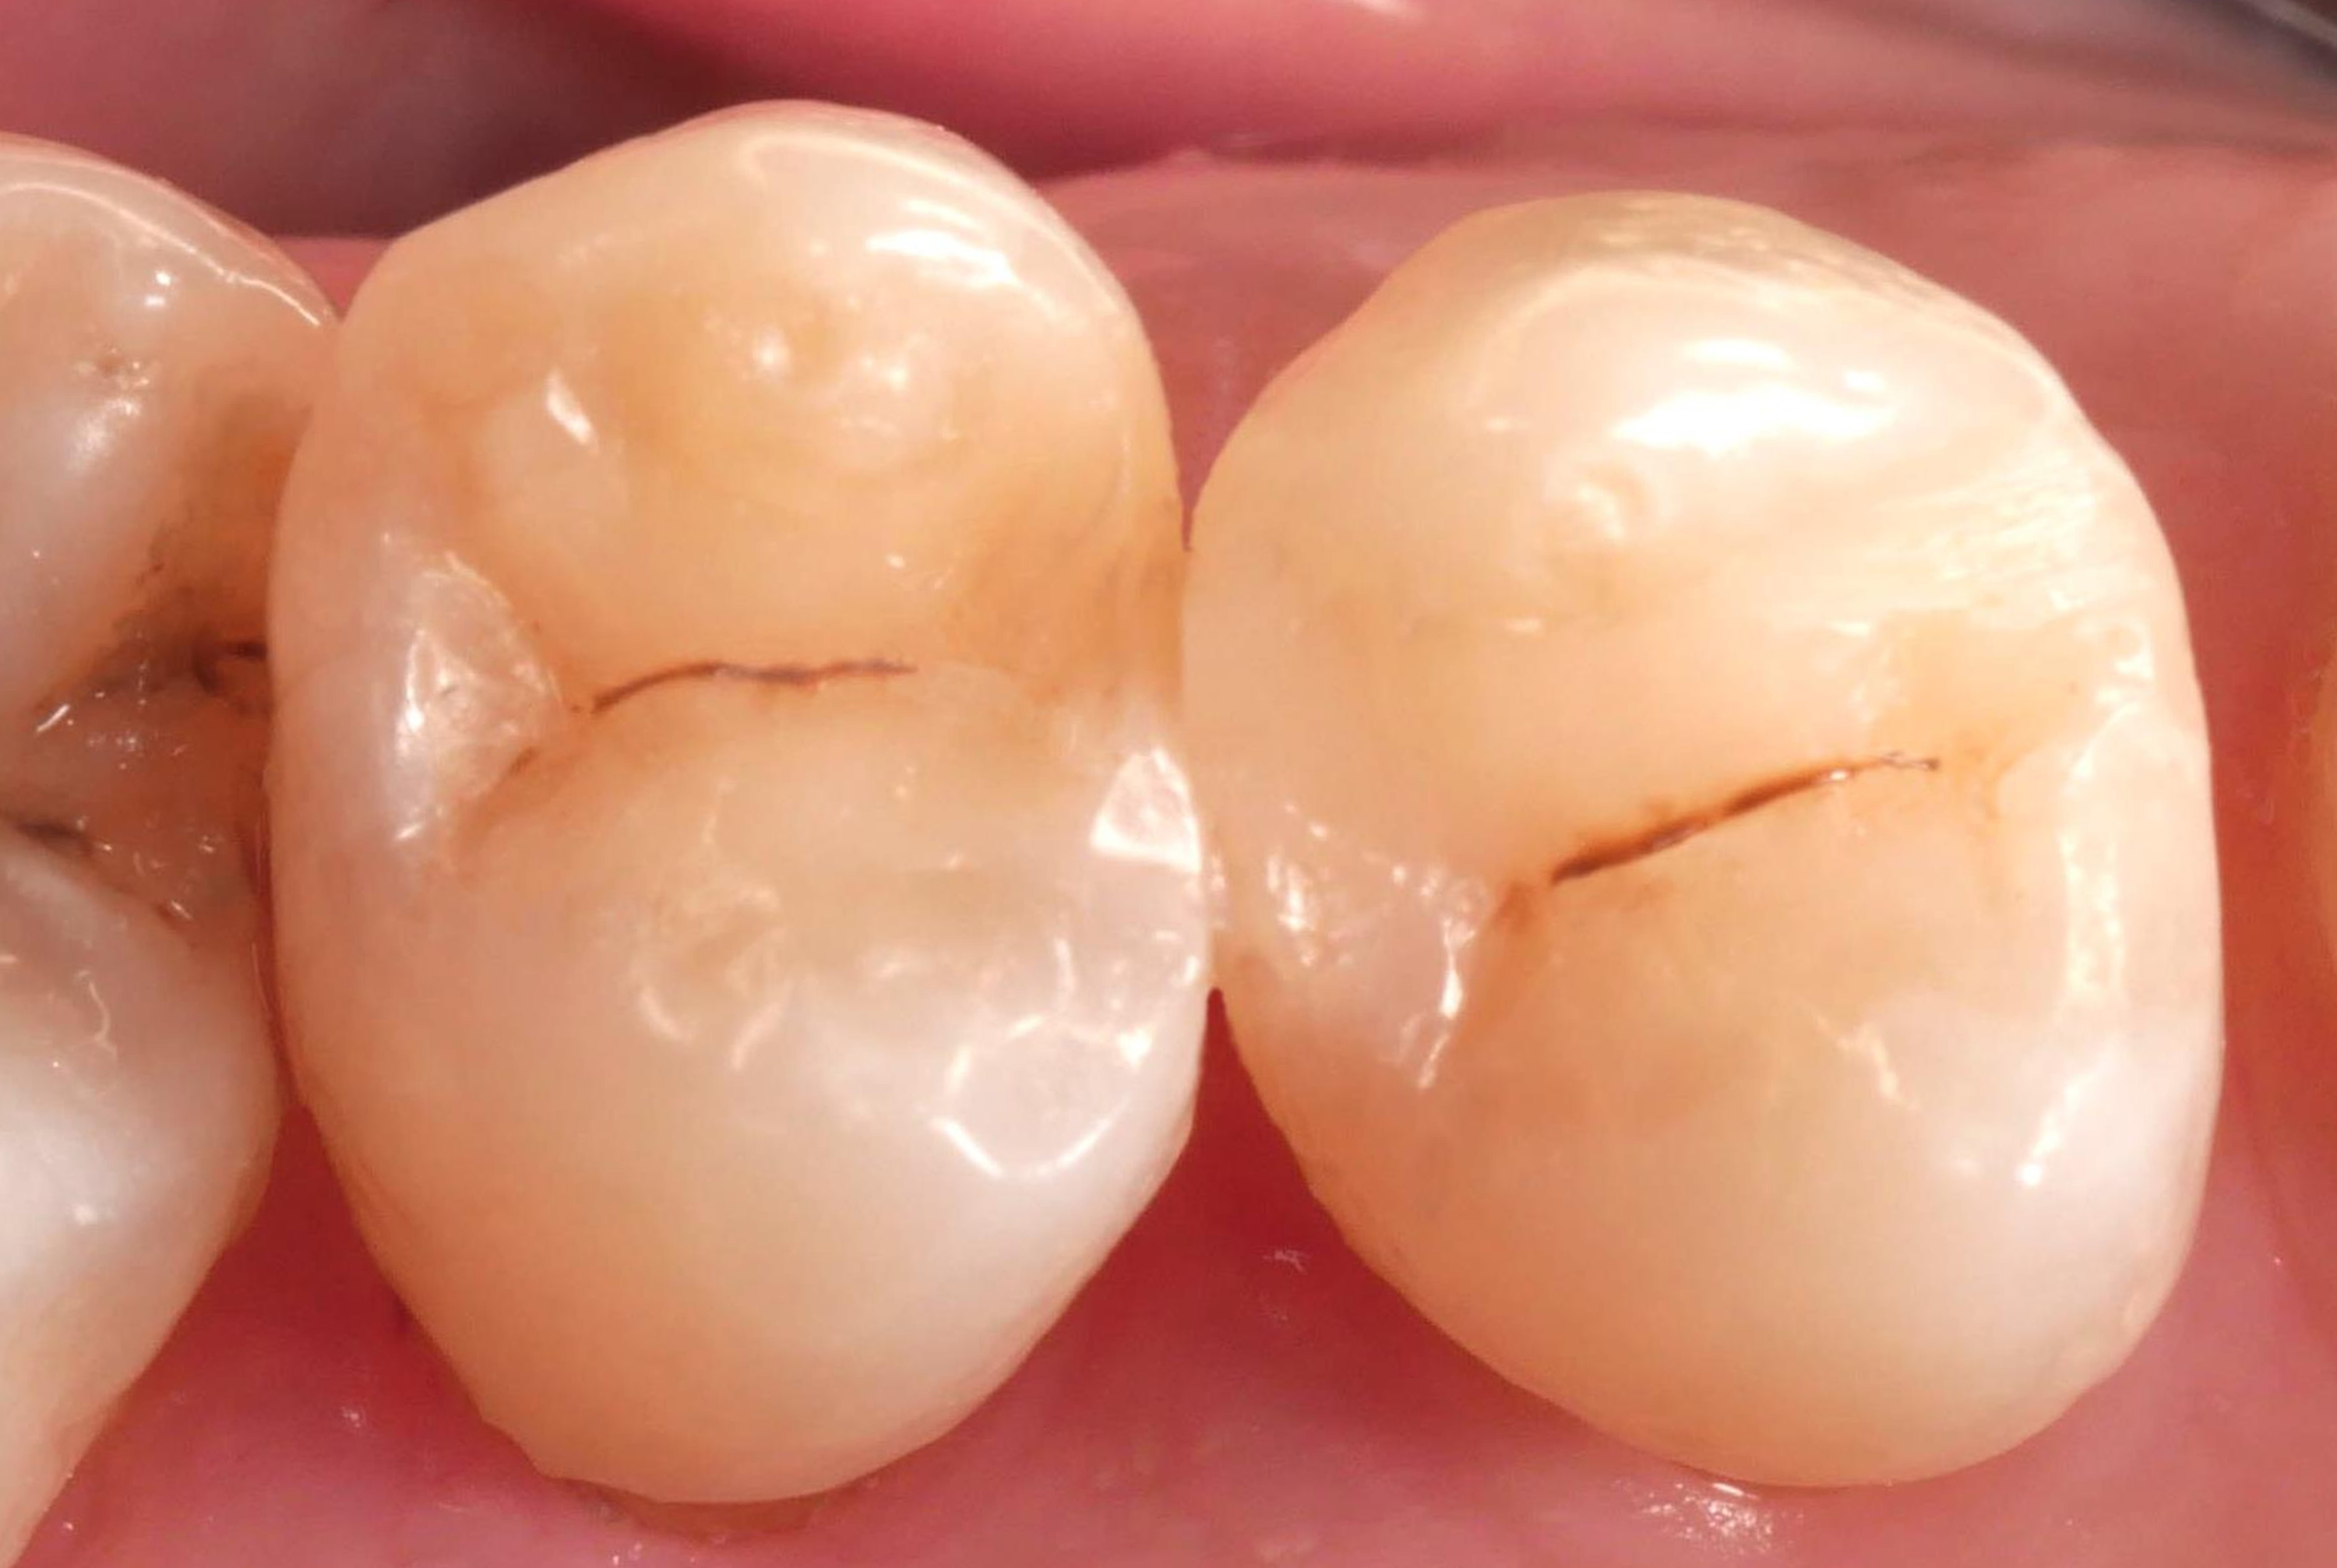

65-letni pacjent zgłosił się z istniejącymi, nieszczelnymi wypełnieniami kompozytowymi, które wymagały wymiany w celu usunięcia zmian próchnicowych i odbudowy struktury zęba (ryc.1).